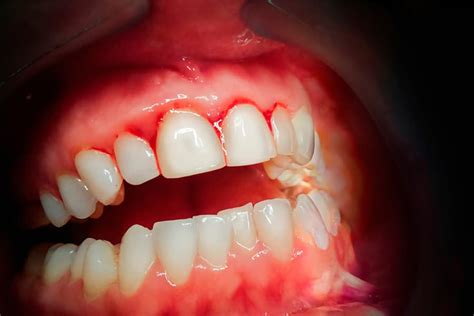

El sangrado de encías es un problema común que puede ser un signo de gingivitis o periodontitis. Según un estudio publicado por GSK, el 40% de la población sufre problemas de encías, lo que lo convierte en el tercer trastorno bucodental más común en España. Aunque es común, no hay que restarle importancia, ya que una encía sana no tiene que sangrar.

Si sangran las encías es porque nos están avisando de la presencia constante de inflamación, muchas veces de causa bacteriana. Las encías sangrantes se producen cuando hay una alteración en el equilibrio de las bacterias de nuestra boca. Sucede habitualmente por el acúmulo de placa.

La gingivitis es la causa más frecuente de sangrado de las encías. Esta enfermedad periodontal produce una inflamación de las encías. Suele suceder por la acumulación de placa bacteriana entre los dientes. Si la gingivitis no se trata correctamente, puede derivar en una periodontitis, conocida popularmente como piorrea.